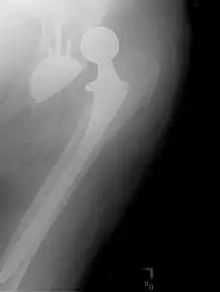

Prothèse totale de hanche

Une prothèse totale de hanche (PTH) est un dispositif articulaire interne qui vise à remplacer l'articulation de la hanche et lui permettre un fonctionnement quasi normal, en tout cas permettant la marche.

Austin Moore a déjà conçu avec Bohlman en 1940 une unique méga prothèse métallique. Le procédé de fixation révolutionnaire qu’il propose pour maintenir la tête fémorale date lui de 1950 : la tête métallique sera portée par une tige fichée dans le canal médullaire du fémur. Depuis cette date la quasi-totalité des implants fémoraux reprendront ce concept de tige intra médullaire.

À cette époque, Moore est le chirurgien de l'Hôpital Psychiatrique de l’État de Columbia, qui dispose de 7000 lits. Les fractures du col du fémur sont fréquentes chez des patients en général âgés, souvent en mauvais état général. Le pronostic de cette lésion est transformé. Quelques jours après l'opération les opérés évoluent dans les couloirs de l'hôpital ce qui est très nouveau. À l'époque la fracture du col du fémur était une cause de mort fréquente chez le vieillard. La prothèse de Moore est en Vitallium. Une fenêtre est pratiquée dans la queue prothétique pour permettre la repousse de l’os. Un trou est placé à la partie supérieure du col. Il sera utilisé, si nécessaire, pour extraire la prothèse.